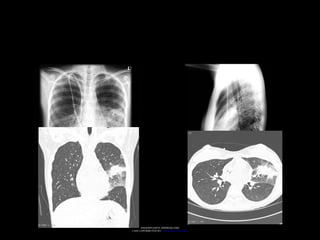

ASPERGILOSIS ALÉRGICA BRONCOPULMONAR

• Pacientes con asma bronquial.

• Dilatación bronquial.

• Involucra bronquios segmentarios y subsegmentarios.

• Reacción compleja de hipersensibilidad.

• Estornudos, fiebre, tos, esputo y dolor torácico.

ASPERGILOSIS ALÉRGICA BRONCOPULMONAR •Pacientes con asma bronquial. • Dilatación bronquial. • Involucra bronquios segmentarios y subsegmentarios. • Reacción compleja de hipersensibilidad. • Estornudos, fiebre, tos, esputo y dolor torácico. Spectrum of Pulmonary Aspergillosis: Histologic, Clinical, and Radiologic Findings Tomás Franquet, Nestor L. Müller, Ana Giménez, Pedro Guembe, Jesus de la Torre, and S. Bagué RadioGraphics 2001 21:4, 825-837

• #16 Liberación de IgE e IgG, infiltrados necroticos y eosinofilicos. Reacciones alérgicas tipo I y III. 1.Inmediatas o alérgica: Basadas sobre la reacción al IgE 2.Cito-tóxica. 3.De complejos inmunes. 4.Retardadas.

• #19 Allergic bronchopulmonary aspergillosis is caused by hypersensitivity towards Aspergillus spp. in patients with long standing asthma and occasionally cystic fibrosis. The hypersensitivity initially causes bronchospasm and bronchial wall oedema, which is IgE mediated. Ultimately there is bronchial wall damage, bronchiectasis and pulmonary fibrosis. Radiological findings: 1. Fleeting pulmonary alveolar opacities (common) 2. Central, upper lobe saccular bronchiectasis (hallmark) 3. Mucus plugging (’finger in glove appearance’) and bronchial wall thickening (common) 4. Chronic diseas http://images.radiopaedia.org/images/191/9e9c374ff90be958fef2ed939a042d_gallery.jpg e may progress to

• #20 Dedos de guante.